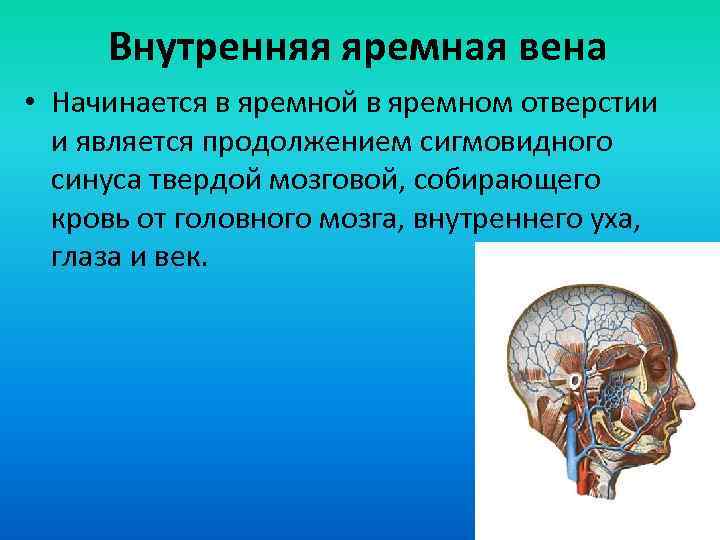

Анатомия внутренней яремной вены: КТ изображения